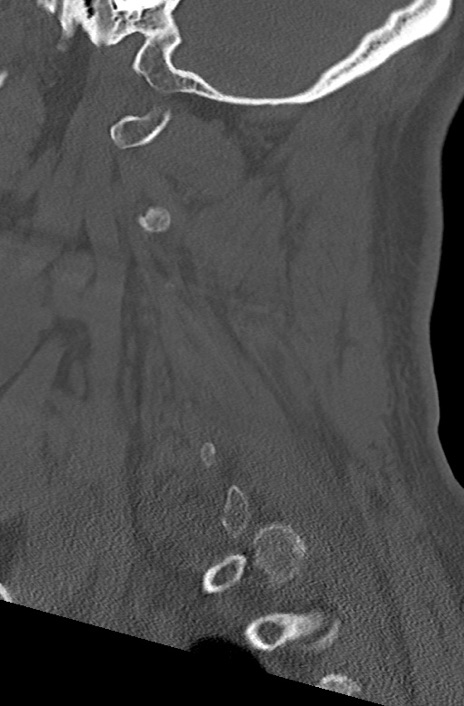

頚椎CT

横断像